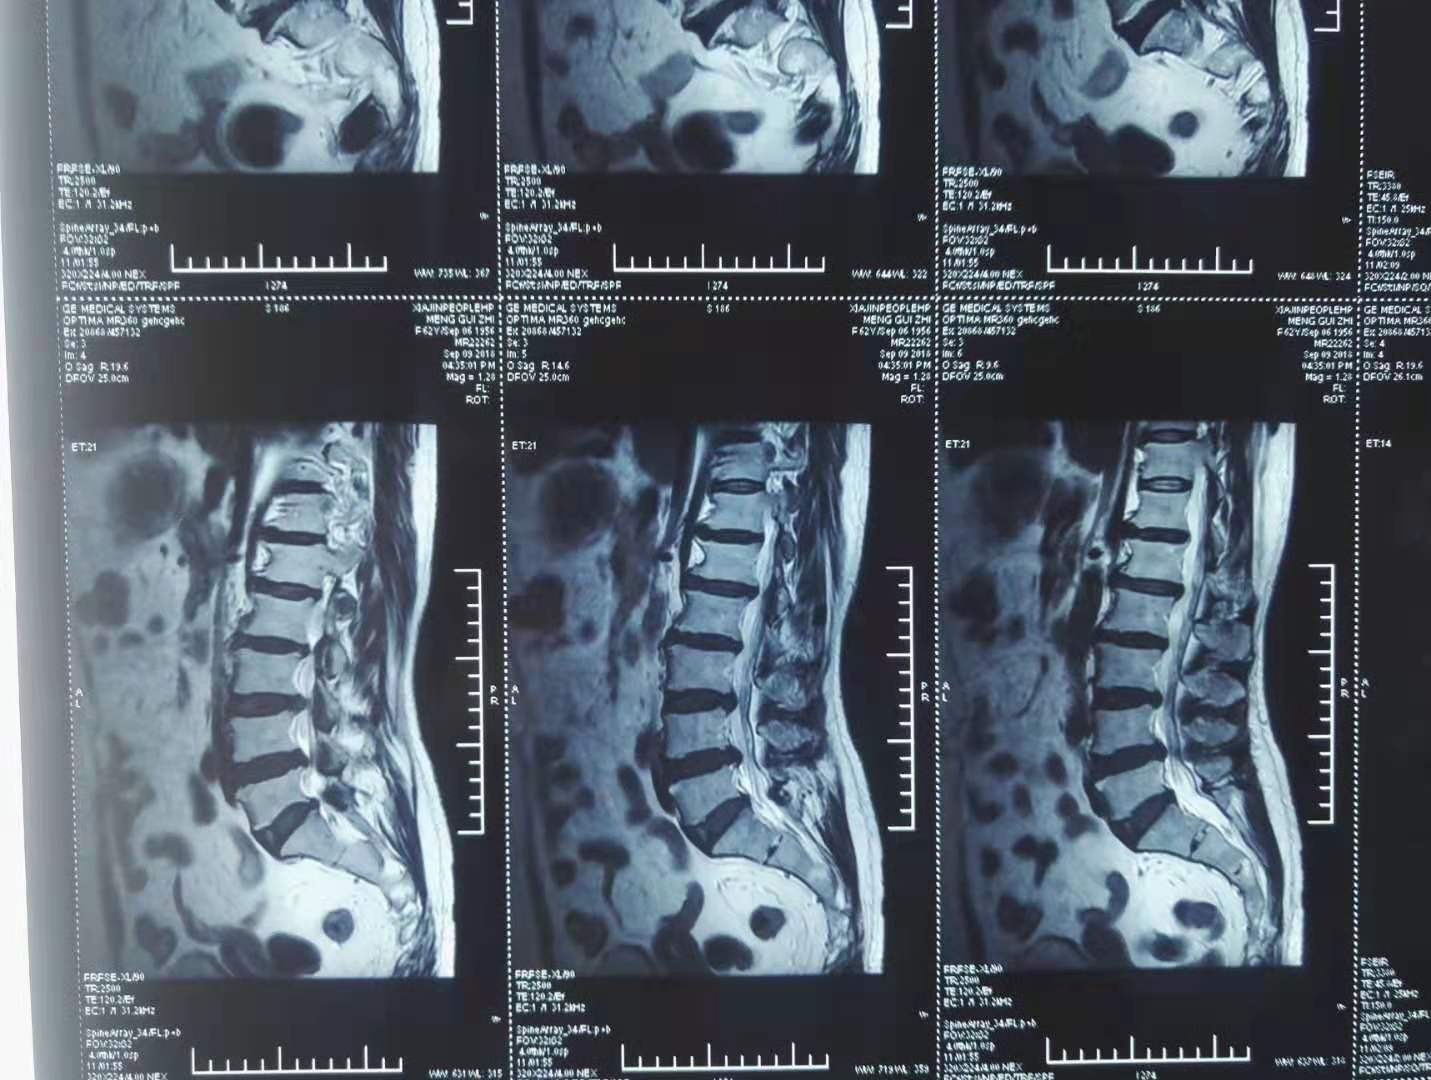

经典医案13

2022.08.03